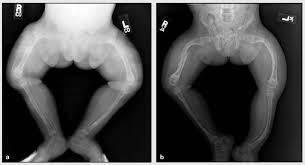

1. Brazos y piernas arqueadas

1. Cifosis

1. Escoliosis (curvatura de la columna en forma de "S")

1. llamada osteogénesis imperfecta severa, las personas con este tipo presentan muchas fracturas al comienzo de su vida y sufrir graves deformidades óseas.